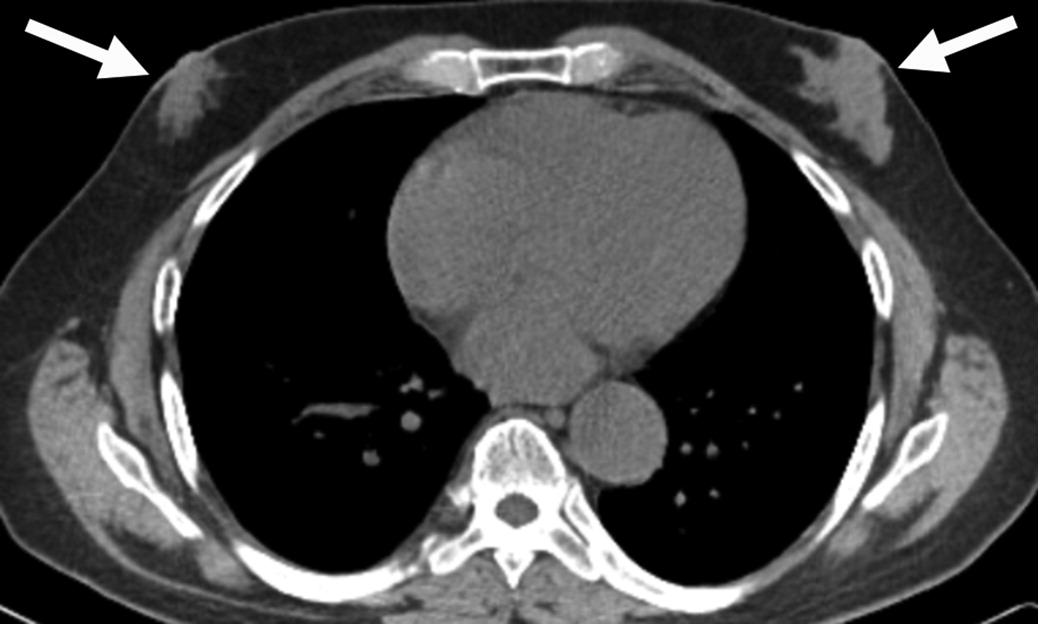

Osteoartropatia Ipertrofica (HOA) in un uomo di 56 anni con noto tumore al polmone.

L’indagine scintigrafica evidenzia una caratteristica ipercaptazione lineare corticale lungo le diafisi delle ossa lunghe tubolari (e bilateralmente a livello zigomatico). Questo pattern simmetrico e periferico è noto come segno del “binario del tram” (tram-track sign).

L’imaging tradizionale conferma la base fisiopatologica del reperto scintigrafico, mostrando una reazione periostale (apposizione di nuovo osso lamellare) a livello metadiafisario.

L’osteoartropatia ipertrofica (che in questo caso rappresenta una sindrome paraneoplastica, spesso secondaria a tumori polmonari) è caratterizzata da una classica triade clinico-radiologica: periostite diffusa delle ossa lunghe, ippocratismo digitale (dita a bacchetta di tamburo) e manifestazioni artritiche/artralgiche. La scintigrafia ossea è estremamente sensibile nell’identificare l’attività periostale in fase precoce.